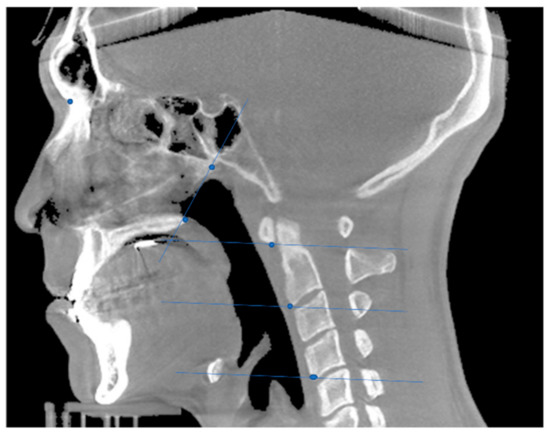

| Reference Points | |

| PNS | Most posterior point of palate |

| VP | Most posterior point of vomer |

| CV1 | Most anterior inferior point of anterior arch of atlas |

| CV2 | Most anterior inferior point of anterior arch of second vertebra |

| CV4 | Most anterior inferior point of anterior arch of fourth vertebra |

| PNS-Vp plane | The plane was perpendicular to the midsagittal plane passing through the PNS and the Vp. |

| CV1 plane | The plane was parallel to the natural head position plane passing through CV1. |

| CV2 plane | The plane was parallel to the natural head position plane passing through CV2. |

| CV3 plane | The plane was parallel to the natural head position plane passing through CV3. |

| CV4 plane | The plane was parallel to the natural head position plane passing through CV4. |

| Nasopharynx | From PNS-VP plane to CV1 plane |

| Oropharynx | From CV1 plane to CV2 plane |

| Hypopharynx | From CV2 plane to CV4 plane |